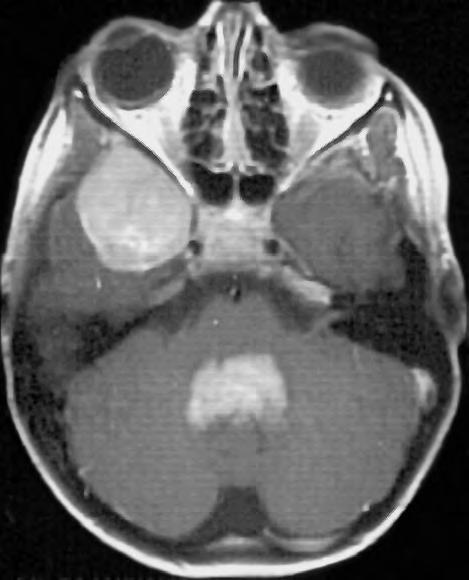

Expanzivní ložisko vCNS může být někdy způsobeno benigním patologickým procesem (abscesem, kavernomem, meningeomem), ale může jít také ometastázu známého nebo doposud ukrytého tumoru, viz obr. 1.4 a1.5. Do mozku často metastazují následující tumory: bronchogenní karcinom, obzvláště jeho malobuněčná varianta, karcinomy prsu aledvin. V80 %případů jsou tyto metastázy uloženy supratentoriálně.

Obr. 1.4 Miliární metastázy mozku bronchogenního karcinomu s okluzí aquaeduktu a hydrocefalem. MR zobrazení v koronárním řezu v T1 váženém čase po aplikaci kontrastní látky i.v. Bílá šipka ukazuje v tektu umístěnou metastázu blokující svou expanzí aquaedukt.

Metastázy mohou vCNS vytvořit jak solitární, tak ivícečetná ložiska, mohou však také infiltrovat meningy (bronchogenní karcinom, karcinomy prsu ižaludku).

Obr. 1.5 Miliární metastázy mozku bronchogenního karcinomu s okluzí aquaeduktu a hydrocefalem. MR zobrazení v sagitálním řezu v T1 váženém čase po aplikaci kontrastní látky i.v. Bílá šipka ukazuje v tektu umístěnou metastázu blokující svou expanzí aquaedukt.